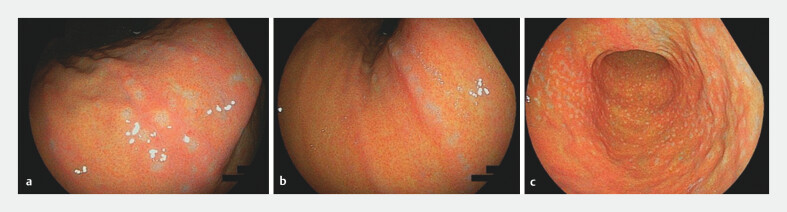

Background and study aims: Map-like redness is a known gastric mucosal finding observed after Helicobacter pylori eradication. Recently, we identified gastric lesions resembling barnacles and observed that they appear more commonly in cases of post- H. pylori infection. This study aimed to investigate clinicopathological characteristics of these barnacle-like lesions.

Results: In total, 413 patients (208 women) were included in the analysis after excluding 23 patients based on exclusion criteria. Barnacle-like lesions were identified in 66 patients (16.0%), most frequently around the gastric angle, and were significantly more common in patients with mild atrophy of the fundic mucosa. Of the 66 patients with barnacle-like lesions, 65 were considered to have a post- H. pylori infection status and one was currently infected. Histopathological examination revealed intestinal metaplasia in 54 (83.1%) of the 65 biopsies from barnacle-like lesions. By contrast, all 17 biopsies from surrounding mucosa showed normal fundic mucosa without inflammation or atrophy.

Conclusions: Barnacle-like lesions are a characteristic endoscopic finding of gastric mucosa post-infected with H. pylori and are histopathologically consistent with intestinal metaplasia.